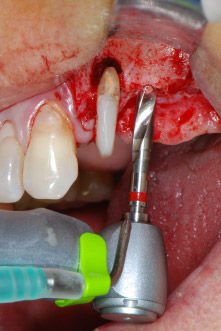

En el siguiente paso, los lechos del implante se prepararon en las posiciones 25 y 26 con instrumentos rotatorios, utilizando un contra-ángulo con un coeficiente de transmisión de 20:1 (WS-75 L, W&H), junto con el nuevo potente motor de implantes Implantmed de W&H (figuras 8 y 19).